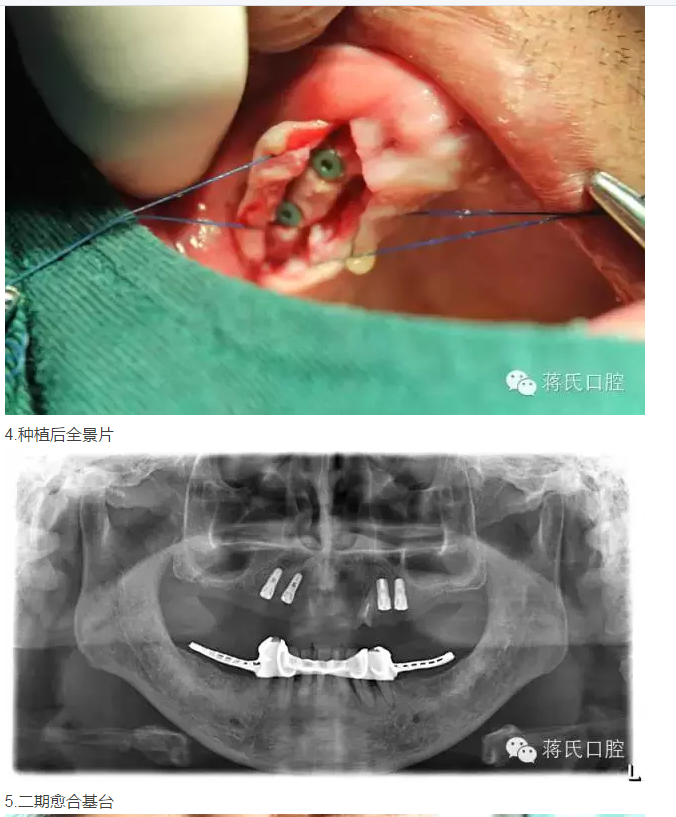

3兩側(cè)四五區(qū)種植共4顆